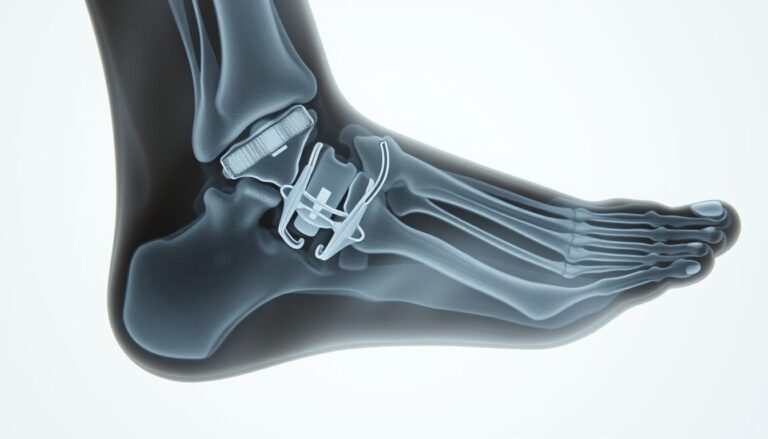

Rehabilitacja po operacji haluksa jest kluczowym aspektem, który wpływa na proces odzyskiwania pełni…